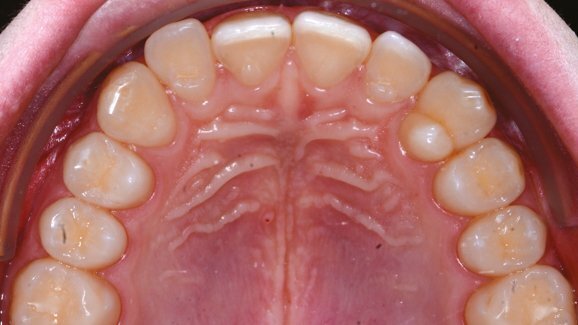

È presentato il caso di un paziente di 20 anni che richiede il miglioramento estetico del suo sorriso e la risoluzione dell’affollamento in entrambe le arcate in tempi ridotti. L’arcata superiore presenta un grado moderato di disallineamento nel settore estetico. Gli incisivi laterali risultano vestibolarizzati rispetto ai centrali (Fig. 1). La foto frontale intraorale evidenzia un overjet e overbite nella norma (Fig. 2). L’affollamento dentale è evidente nello stesso settore anche in arcata inferiore (Fig. 3).

Il trattamento ortodontico è stato eseguito con F22 Aligner (Sweden & Martina). Il setup digitale, l’esecuzione delle procedure di stripping, l’applicazione dei grip point così come i controlli ad ogni appuntamento sono stati interamente eseguiti dallo specialista. Sono stati pianificati 8 step per ogni arcata per una durata complessiva di trattamento di soli 4 mesi. Sugli elementi 4.3 e 3.4 sono stati posizionati i grip point vestibolari per la correzione di rotazioni maggiori di 20° mentre sugli elementi 1.2, 2.2, 3.2 e 4.2 sono stati posizionati sulla superficie linguale trattandosi di un settore estetico. Tutti i grip point e l’intera quantità di stripping, nella maggior parte dei siti non superiore a 0.3 mm, sono stati eseguiti al primo appuntamento appena prima della consegna della prima mascherina.

Il paziente ha indossato gli allineatori circa 22 ore al giorno ed ogni allineatore è stato indossato per 15 giorni. La nota particolarmente interessante è che la maggior parte dell’affollamento in entrambe le arcate viene risolto grazie alla sola vestibolarizzazione delle corone dovuta all’applicazione di una forza singola sulla superficie linguale delle corone, movimento altamente predicibile e che avviene in maniera agevole con questo tipo di apparecchiatura (Fig. 4). Le foto finali del trattamento evidenziano un parallelismo tra ciò che era stato pianificato digitalmente dall’ortodontista e il risultato finale (Figg. 5, 6).